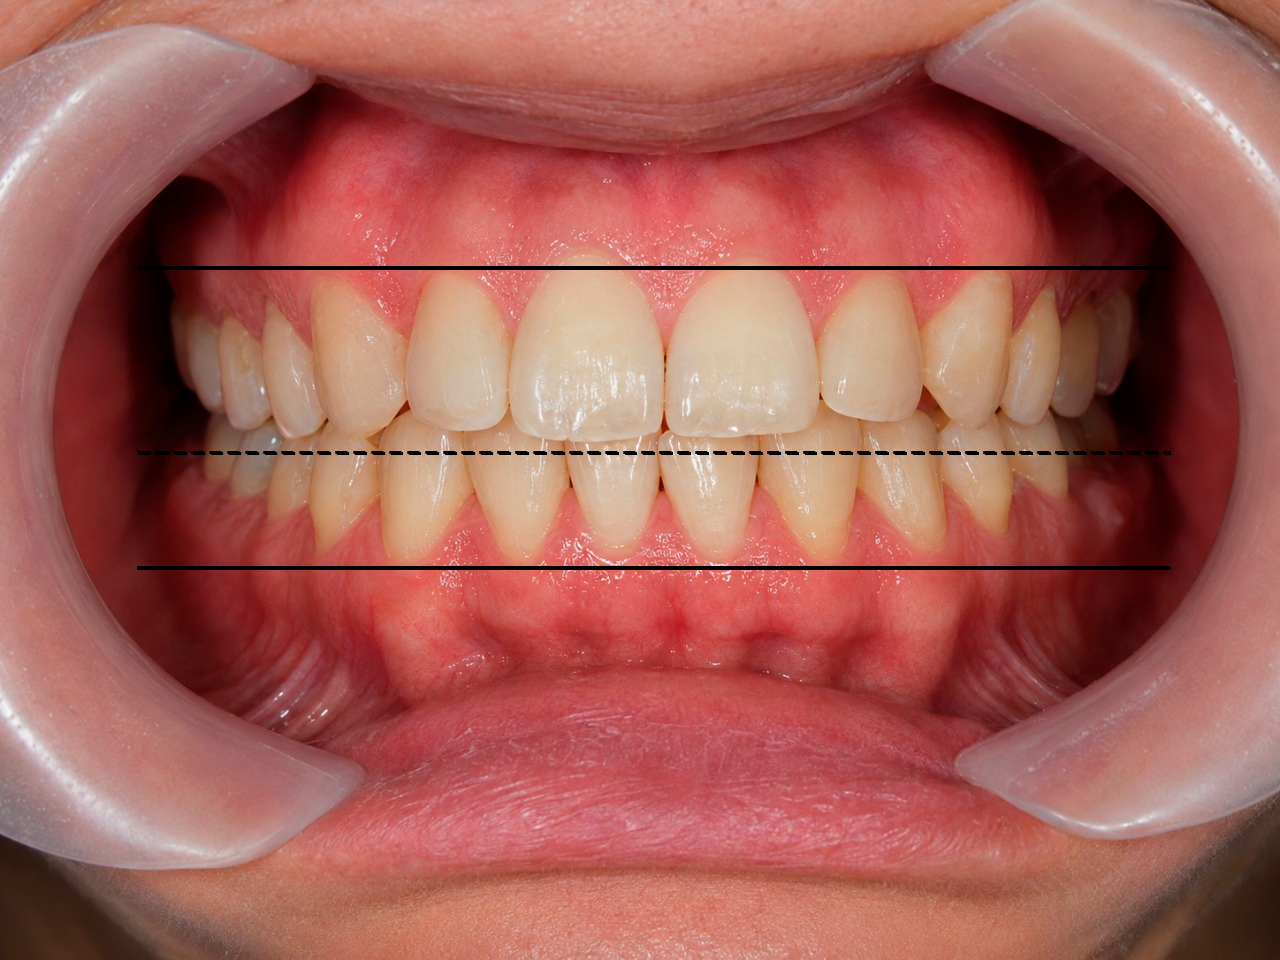

Привлекательная улыбка имеет свои вполне четкие стандарты:

- Линия верхних зубов (арка улыбки) должна быть параллельна нижней губе.

- Улыбка должна быть широкой. Чем больше зубов видно в момент улыбки, тем более привлекательной и открытой она воспринимается окружающими.

- Средняя линия улыбки должна совпадать с центром лица.

- Кроме того, чем заметнее при улыбке верхние зубы пациента, тем моложе он кажется. И, наоборот, демонстрация при улыбке нижних зубов добавляет годы.

Поэтому ортодонт обязательно учитывает все выше перечисленные параметры и планирует

такое передвижение зубов, чтобы, исходя из имеющихся возможностей, сделать улыбку

пациента максимально приближенной к идеалу. После грамотного ортодонтического лечения

пациент будет выглядеть более молодым и привлекательным без всякой пластической хирургии.

Результаты таких расчетов тоже отражаются в плане лечения.